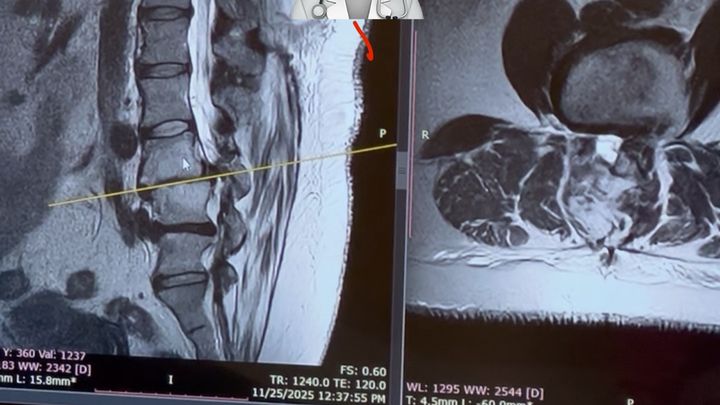

In the last few months, my condition has worsened to the point where, I can’t work, I can’t drive, I can barely stand long enough to cook or clean.I can’t even sit down long enough to do my daughter’s hair without severe pain.After months of struggling, doctor visits, and physical therapy 3x a week, I finally received the news I feared.

I need major back surgery.

It’s the only way for me to keep walking, keep caring for my family, and continue being the mom and daughter they need. The surgery requires 1 week in the hospital, 4–6 months of recovery at home, continued physical therapy afterward, and the heartbreaking reality that I won’t be able to work at all during this time.As the sole provider, this has put us in a frightening situation.